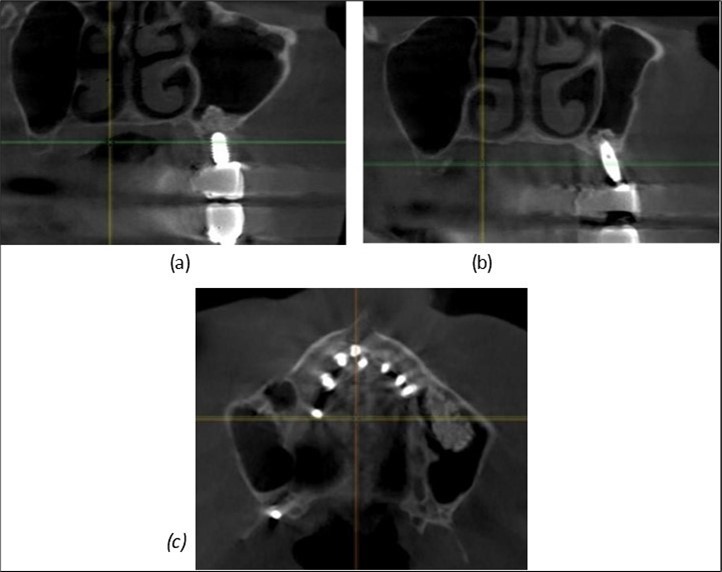

Figure 9.Implants in the pterygoid plateau area: (a) TPG implant fixed in the maxillary-sphenoid junction area, quadrant 1; (b) TPG implant fixed in the maxillary-sphenoid junction area, quadrant 2.

Implants in the pterygoid plateau area: (a) TPG implant fixed in the maxillary-sphenoid junction area, quadrant 1; (b) TPG implant fixed in the maxillary-sphenoid junction area, quadrant 2.